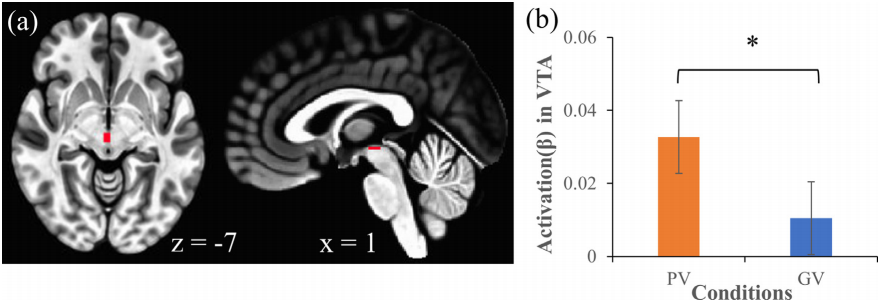

第二,才是原文中关于多巴胺的内容:两类视频都会激活大脑黑质(SN),但个性化推荐视频还会激活腹侧被盖区(VTA),而 SN 和 VTA 都与多巴胺的分泌有关。

这仅仅意味着在个性化推荐的加持下,短视频对大脑奖赏系统的激活更为强烈。

上瘾与沉迷

观看视频时,视频的刺激会激活大脑的奖赏通路。奖赏通路内的神经元会释放大量的多巴胺,让大脑将特定的行为与快乐联系起来,使人们产生再次执行这个行为的渴望。2019 年的一项新研究表明,小脑可能也是奖赏通路的一部分,它与腹侧被盖区直接相连,而腹侧被盖区则是处理奖赏的核心区域之一 [12]。腹侧被盖区和黑质(substantia nigra)会共同强化那些能够获得奖励的特定行为。其中,黑质的神经元倾向于编码信息的显著性,让这些信息更容易从其他噪音信息中脱颖而出。同时,腹侧被盖区的神经元会对奖励的价值高低进行编码。这个过程允许大脑着重处理视频提供的感官信息,并让这些刺激显得弥足珍贵。研究发现,相较一般视频,个性化推送的视频会显著激活腹侧被盖区,说明这些算法推荐的视频对于观看者有更高的奖励价值,也会让人更容易上瘾。

(a)腹侧被盖区在 MNI 脑模板上的位置。

(b)相较一般视频,在观看算法推荐的视频时,腹侧被盖区的活跃程度显著更强。

—

参考文献 [4]